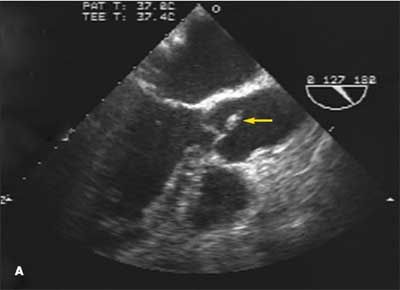

A 55-year-old woman complained of fever, weakness, and generalized malaise. Twelve hours after admission, she had hypotension, atrial fibrillation, and worsening respiratory distress; 24 hours after, she had a cardiac arrest. This echocardiogram showed inferior wall hypokinesis, along with a ventricular septal defect in the inferoseptum, a complication of myocarditis.

Myocarditis, with focal or diffuse inflammation, may be of infectious or noninfectious origin. Viral infections are the most common infectious causes, although the true incidence of viral myocarditis is unknown. Other causes of myocarditis include autoimmune diseases and a hypersensitivity response to drugs.

The clinical presentation of myocarditis varies, ranging from asymptomatic to a fulminant picture, which may include heart failure, arrhythmias, and cardiogenic shock.

Definitive diagnosis requires an endomyocardial biopsy, which should be performed when fulminant or giant cell myocarditis is suspected.